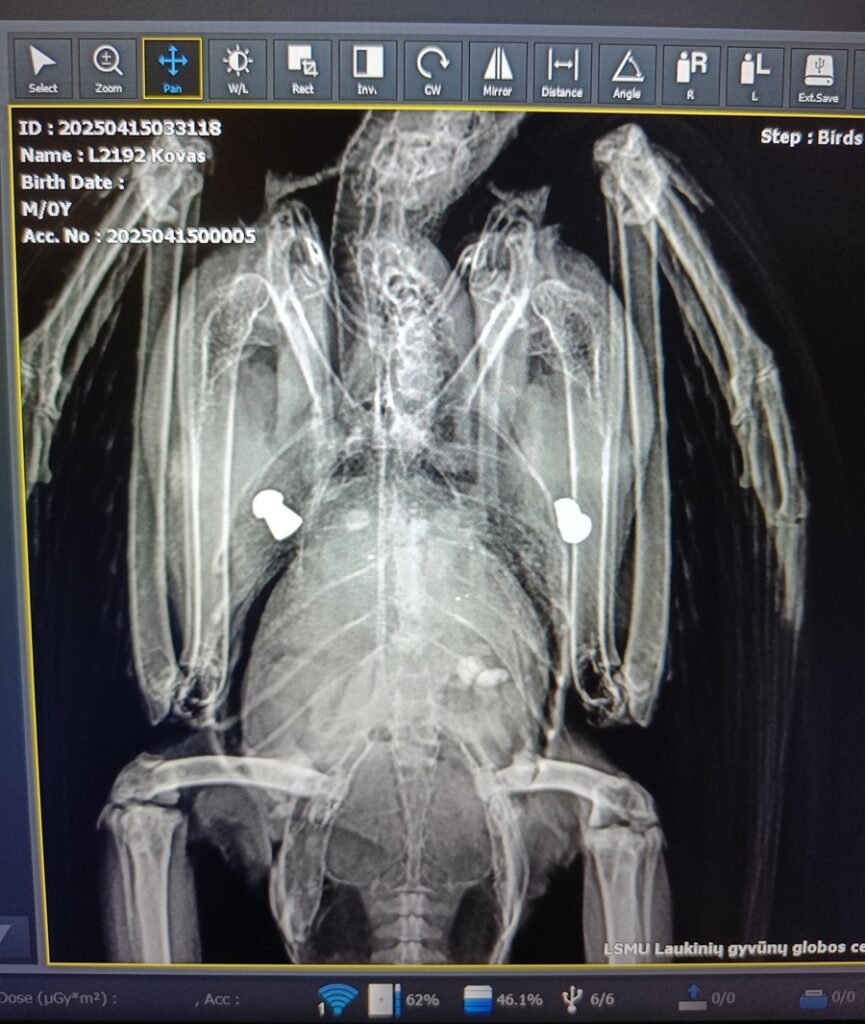

Susiduriama ir su tyčiniais sužalojimais: praėjusiais metais 14 gyvūnų buvo sužaloti šaunamaisiais ar pneumatiniais ginklais. Dažniausiai nukenčia varninių šeimos paukščiai ir baltieji gandrai (Ciconia ciconia).

„Pernai balandį į centrą pateko kovas (Corvus frugilegus), kurio kūne rentgeno tyrimo metu aptikome du pneumatinio ginklo šovinius. Jie buvo įstrigę ties šonkauliais, šauta iš dviejų skirtingų pusių. Šovinius pašalinome chirurginiu būdu, tačiau paukštis neišgyveno. Tikėtina, kad be mechaninių pažeidimų, prisidėjo ir švino toksikozė“, – pasakojo LGGC veterinarijos gydytojas Rokas Matevičius.